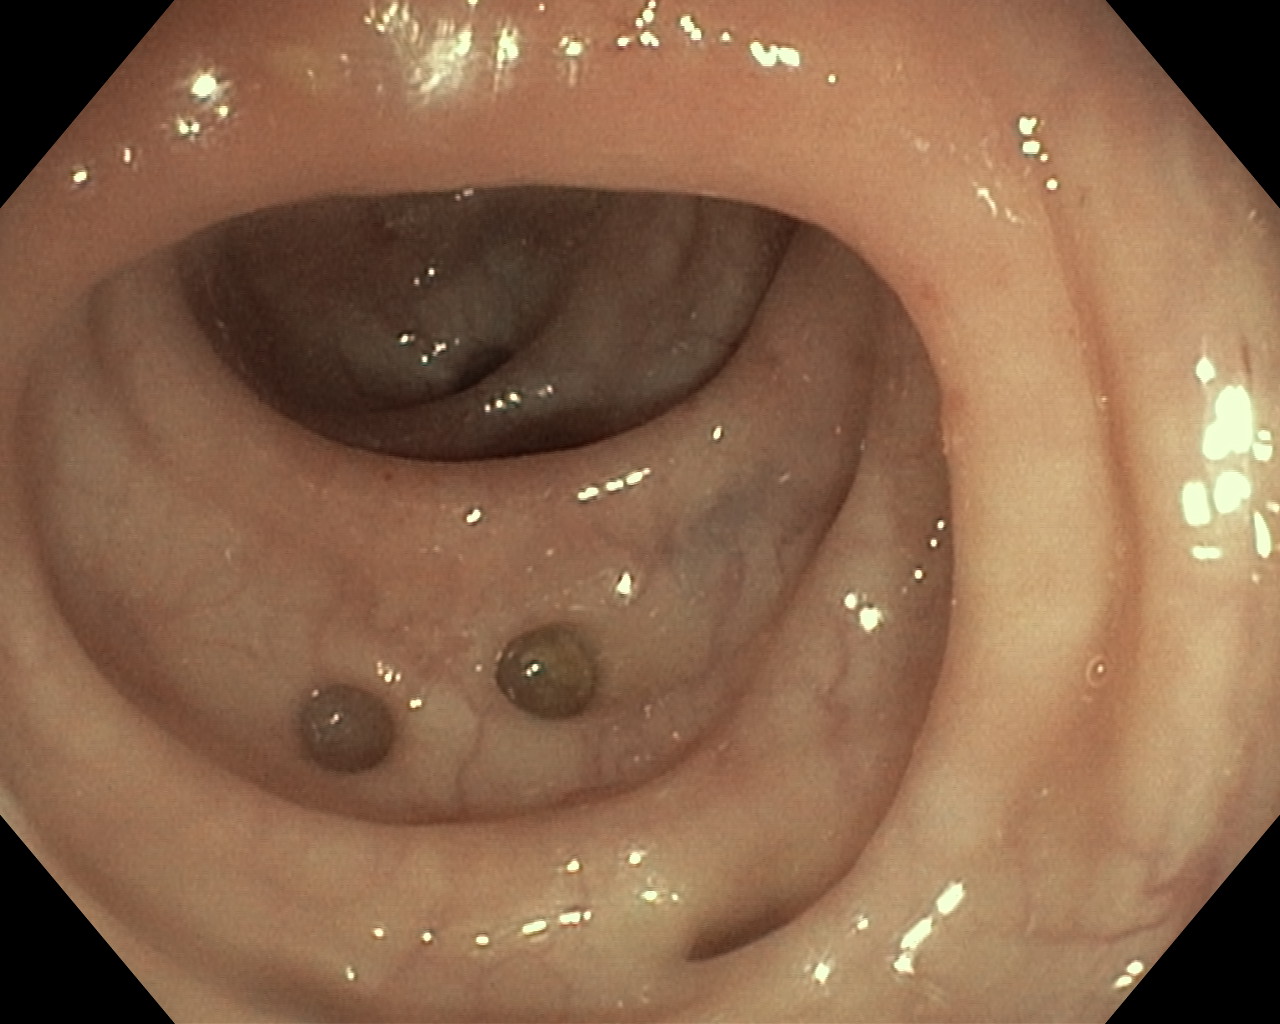

Uchyłki